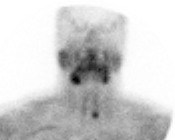

Intra-operative photograph of thyroid lesion

Papillary thyroid carcinoma